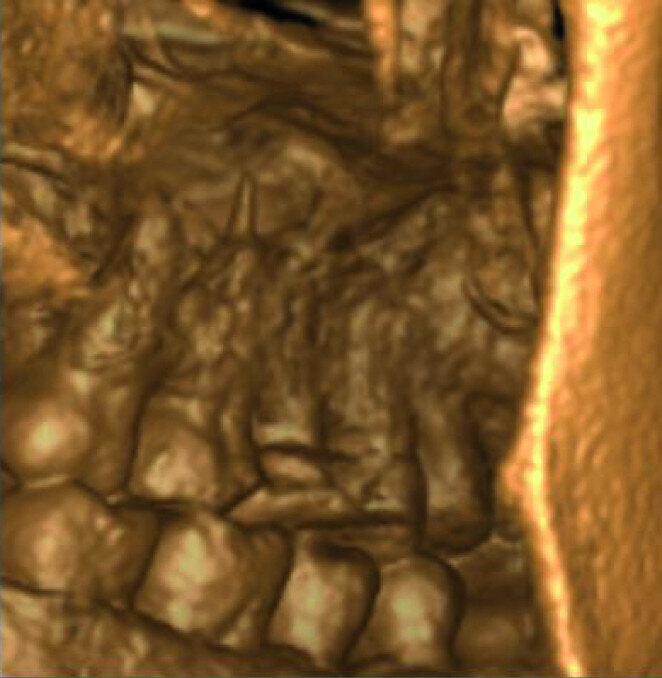

A patient was referred to the office with problems related to separated files. He was a pilot and was complaining of pus draining from his nose when flying. From the preoperative radiograph (Fig. 1), it was clear that there were two separated file fragments in the mesial canals and one cone passing beyond the apex in the palatal root. I requested an iCAT scan, and from this, the left sinus was clearly almost full with inflammatory fluid (Fig. 2) and the cone in the palatal canal was clearly emerging into the sinus. We could also see the two separated files in the two mesial canals clearly in the MPR view (Figs. 3 & 4), as well as another file entering the sinus and not attached to the canal (Fig. 5). We could see the file using different filters (Figs. 6–9), as well as the inflammation inside the sinus and the separated file. We additionally gained a better idea of the location of the cone protruding from the palatal canal into the sinus.

The treatment plan was to try to solve it with a conventional approach and if necessary to perform microsurgery to save the tooth. With the help of H-files, I managed to retrieve the cone from the palatal root, but the files inside the mesial root were impossible to bypass or even to reach with ultrasonic tips. I decided not to overdo it in order to avoid creating an additional problem, like perforating the canal, and decided to seal the canals (Fig. 10). A surgical approach was immediately taken for the mesial canals, cutting 3 mm of the mesial root using the Impact Air handpiece (SybronEndo), and this gave me a direct view of the Schneiderian membrane, where the third file was barely hanging (Figs. 11 & 12). I managed to delicate grab it and to remove it (Fig. 13). Figure 14 shows the postoperative situation, after performing retrograde preparation of the mesial canals.